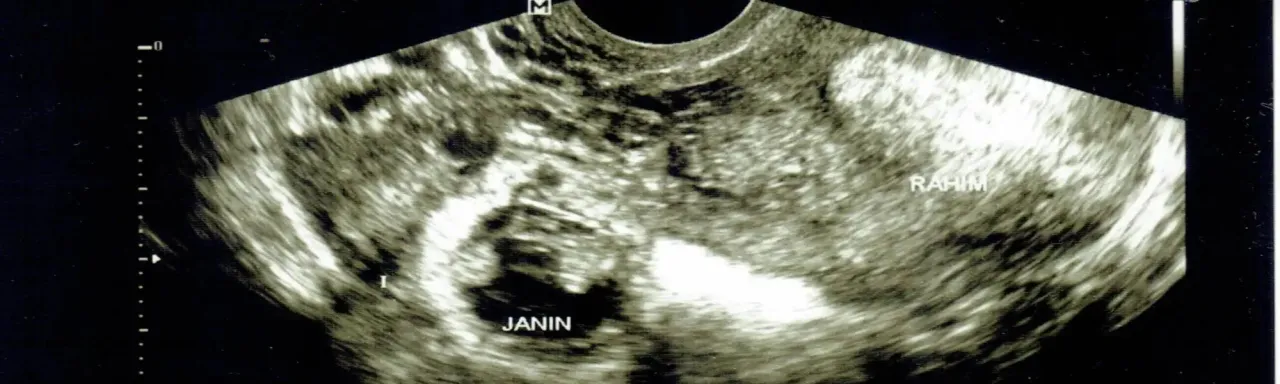

Rola USG przezpochwowego w lokalizacji ciąży

Przezpochwowe badanie ultrasonograficzne jest złotym standardem w lokalizacji ciąży. Pozwala ono na wizualizację pęcherzyka ciążowego i zarodka. W prawidłowej ciąży, pęcherzyk ciążowy powinien być widoczny w jamie macicy już około 5-6 tygodnia ciąży. W przypadku ciąży pozamacicznej, badanie USG może pokazać pustą macicę, a czasem uwidocznić masę ciążową poza macicą, np. w jajowodzie. To badanie jest nieocenione w różnicowaniu ciąży prawidłowej od ektopowej.

Co oznacza "pusta macica" przy dodatnim teście ciążowym?

Sytuacja, w której domowy test ciążowy jest pozytywny, poziom beta-hCG we krwi jest podwyższony, ale podczas badania USG przezpochwowego nie widać pęcherzyka ciążowego w jamie macicy, jest bardzo niepokojąca. Jeśli poziom beta-hCG przekracza tzw. "próg widoczności" (zazwyczaj około 1500 mIU/ml), a macica pozostaje "pusta", silnie sugeruje to ciążę ektopową. W takim przypadku lekarz podejmie dalsze kroki diagnostyczne i terapeutyczne, aby jak najszybciej potwierdzić i rozwiązać problem.